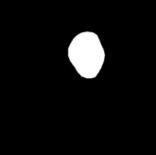

Figure 6 illustrates the segmentation outcomes attained with different neural networks using the same dataset. The enhanced U-Net network proposed in this study is evaluated alongside expert gold standards, Swin-Unet, U-Net, and other well-known network models. The segmentation results from the Swin-Unet network show jagged edges and less smooth nodule edge segmentation, leading to suboptimal outcomes. In the case of U-Net, there are evident under-segmentations with significant discrepancies in the segmented area of some nodules, resulting in inaccurate segmentation results. However, the use of the improved U-Net network introduced in this research produces smoother edges of the segmented thyroid nodules, and the edge contours more closely align with those of the expert gold standard. Moreover, the errors in shape and segmented area are smaller compared to those seen with U-Net and Swin-Unet. The findings suggest that the improved U-Net network provides superior performance in thyroid nodule segmentation.